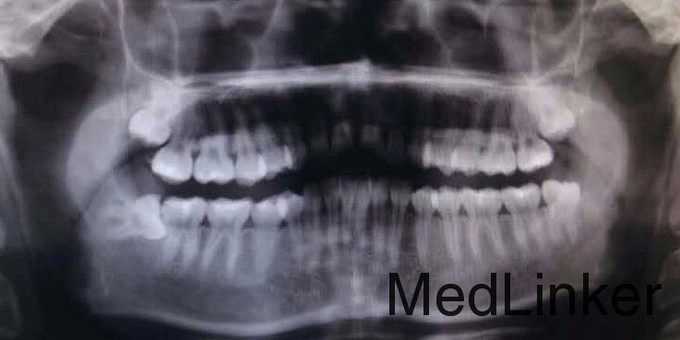

1106下颌水平阻生智齿的拔除光2

右下后智齿一年左右才萌出一点,要求拔除

1106近中水平阻生智齿的拔除光5

水平阻生智齿拔除

1108下颌水平阻生齿拔除光14